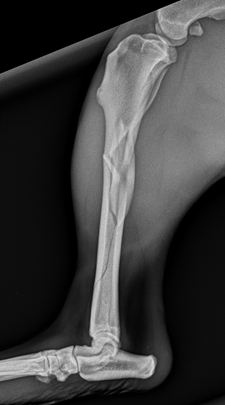

Indie (a 2 year old female Boxer) was out for a walk and jumped onto a slope. She landed awkwardly, cried out and was suddenly unable to bear weight on the leg. She was taken to the Rosemary Lodge Veterinary Hospital where a fracture was suspected. She was given strong pain relief, radiographs were taken and the leg was placed in a support bandage. The radiographs showed that there were fractures of the right tibia and fibula, with a butterfly fragment at the mid shaft tibia, and a spiral fissure extending towards the hock. Indie was subsequently referred to Jon Shippam at Bath Vet Referrals.

Fractures that are very close to, or even involving joints are more demanding to treat. If the joint is involved then accurate reconstruction is essential to avoid severe osteoarthritis and joint pain. If a fracture or fissure extends very close to a joint it creates difficulties placing implants to achieve sufficient stability for the fracture to heal. In this case a CT was performed to check the exact location of the fissures to help with surgical planning.